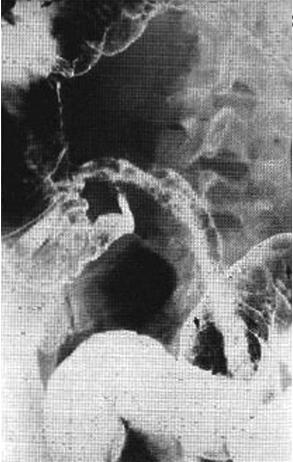

Invertogram d'une

imperforation anal en position decubitus " priera

Mahometa " , Rayon X central est place horizontal

parallelique avec le plan de la table |

Cliche de profile en

position " priera Mahometa " . Le rayon X central

est enplace a horizontal , la cassette est place

perpendiculaire avec la table ( voie en image )

. |